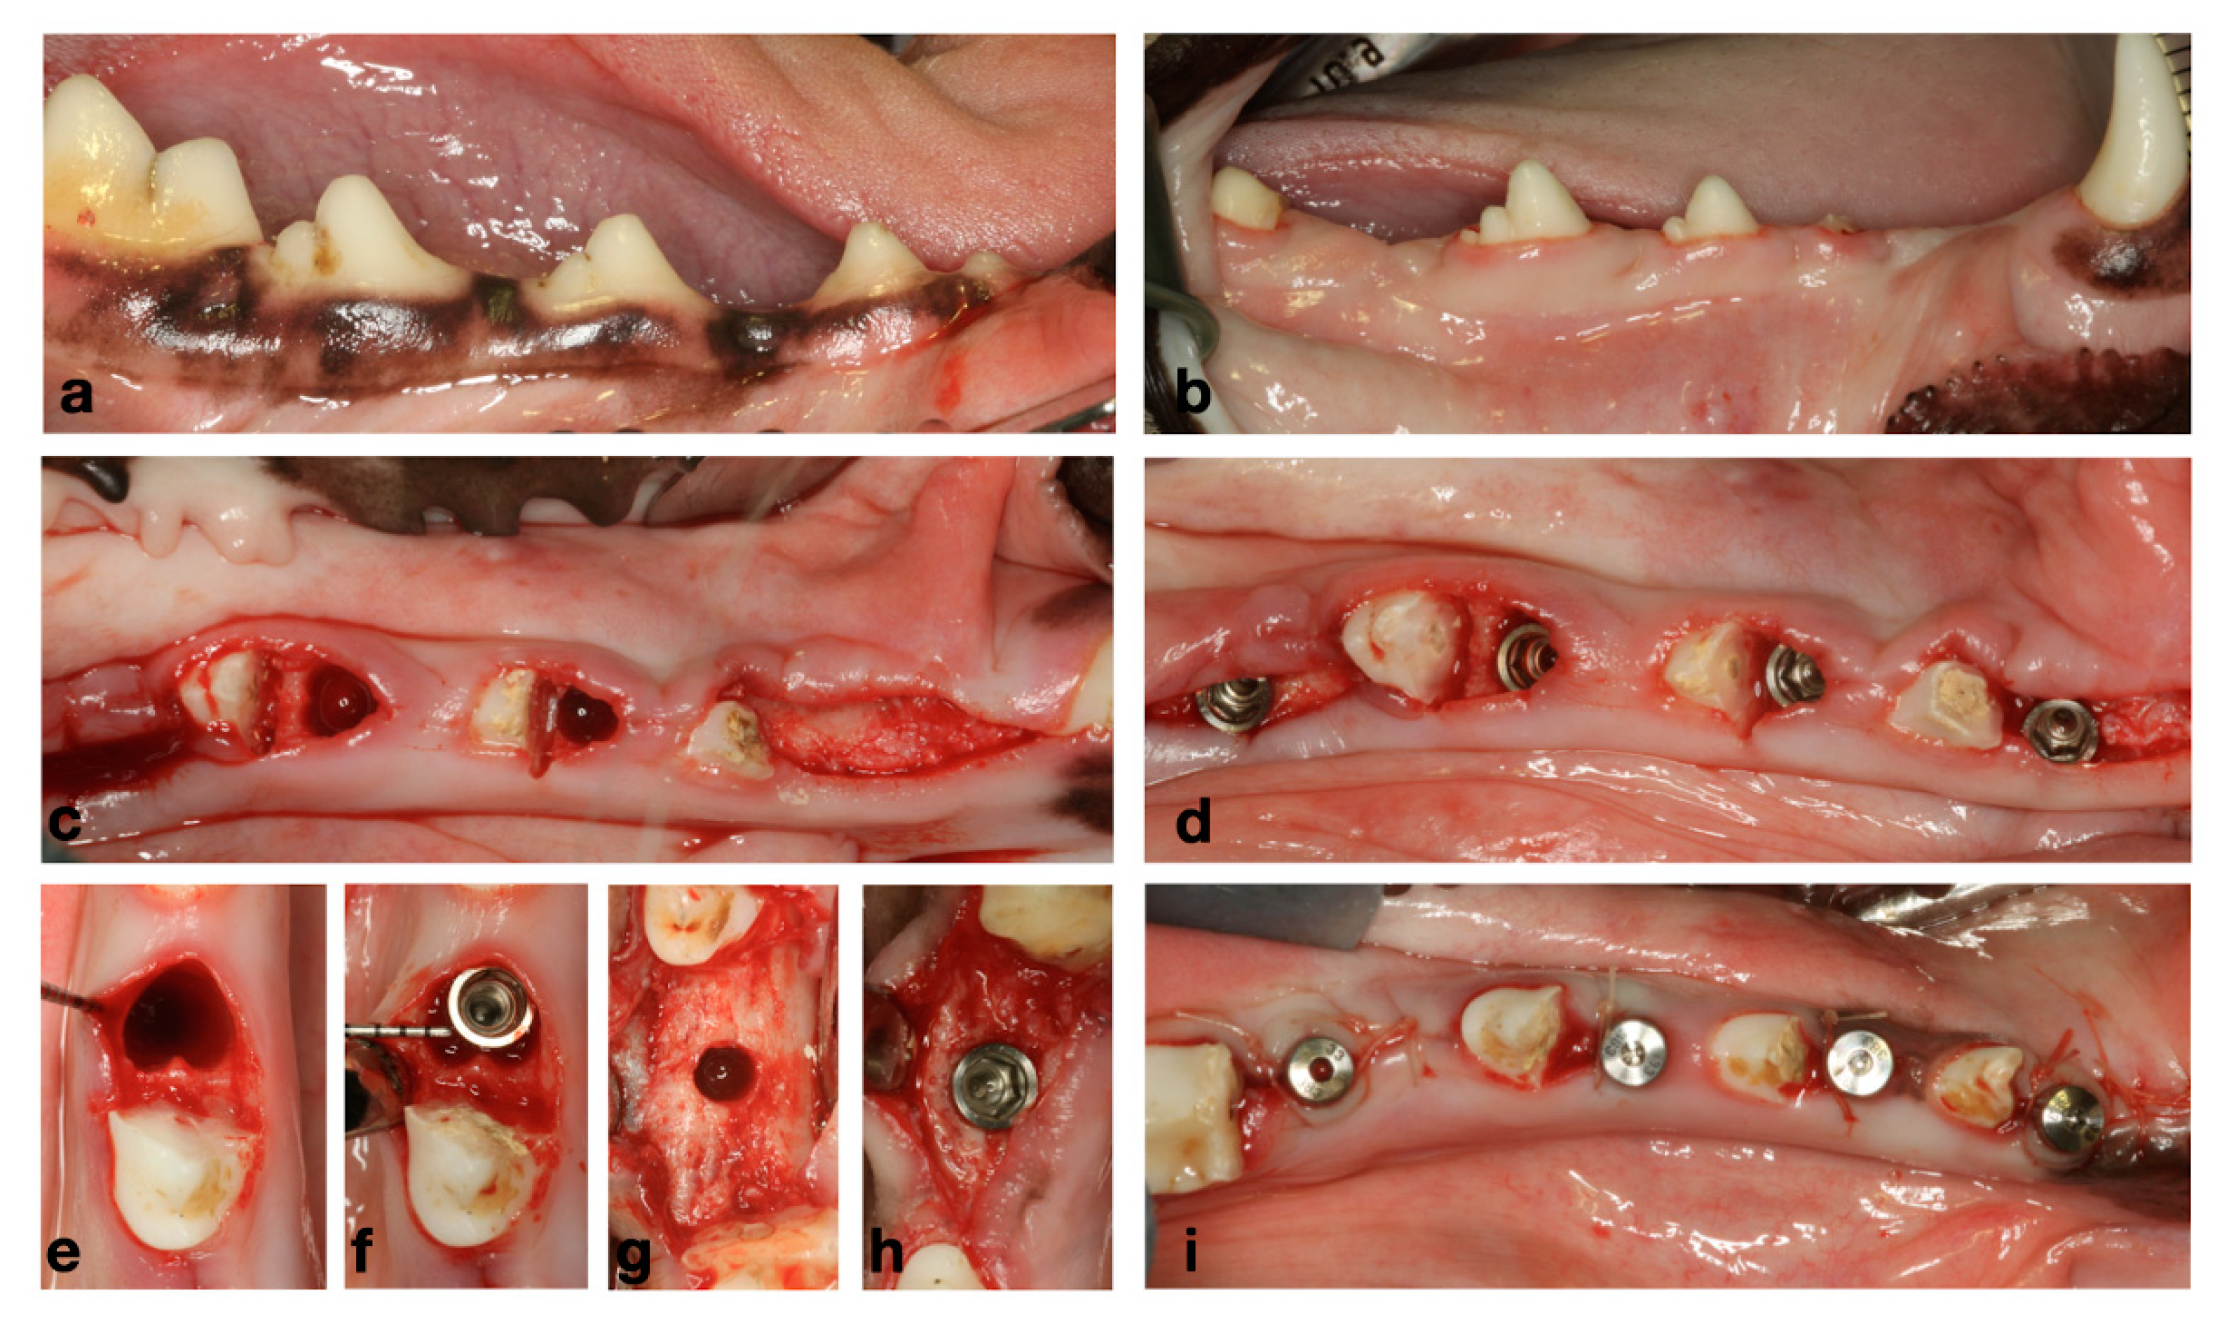

3.1. Preclinical Observations

3.2. Histology and Histomorphometry